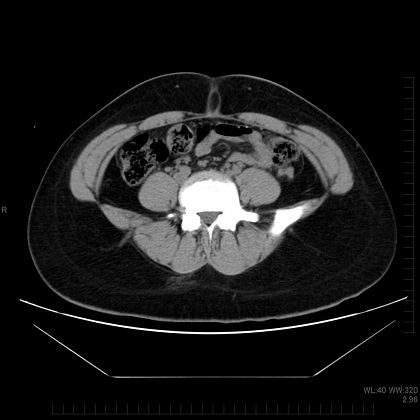

体脂肪には、皮下脂肪と内臓脂肪の2種類があります。指でつまめるのが皮下脂肪、体の奥に隠れているのが内臓脂肪で、それぞれのタイプを皮下脂肪型肥満、内臓脂肪型肥満と呼びます。

内臓脂肪は、わりと最近になってから存在が確認されました。CTスキャンが実用化し、体を輪切りにした画像が容易に得られるようになったからです。こうして画像で見ると、違いは一目瞭然ですね。

内臓脂肪型肥満

皮下脂肪型肥満

画像:『ダイエット外来の減量ノート』(今西康次著)より